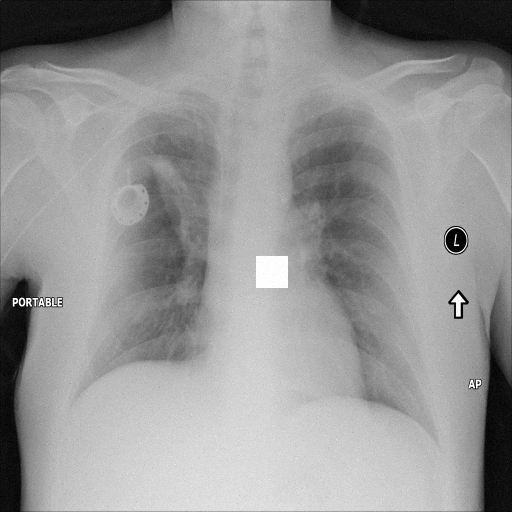

7.2 Qualitative assessment of LDP-processed CXR images

Here, we assume two possible privacy leakage scenarios. To CXR images, we intentionally add features that can lead to the re-identification of the subject appearing in a CXR image. The first feature is an artificial block marker. The second feature is a rare anatomical abnormality known as situs inversus simulated by flipping a CXR image along the vertical axis. Figs. 3(a) and 3(c) show CXR images with the artificial block marker. Fig. 5(a) shows a flipped CXR image to represent a case of situs inversus. We applied DP-GLOW to these CXR images. In Figs. 3(b) and 3(d), the image domain LDP fails to obfuscate the artificial block marker with a moderate privacy budget. In contrast, in Figs. 4(b) and 4(d), DP-GLOW successfully obfuscated the artificial block marker with the moderate privacy budget. On the other hand, the anatomical shape of the chest and the abnormal opacity (hilar regions in the case 1) are preserved. In Fig. 5(b), we observed that the right edge of the heart does not become obfuscated with the image domain LDP. In contrast, in Fig. 6(b), we observed that the right edge of the heart becomes obfuscated and the heart appears at the center of the thoracic cage with DP-GLOW. However, DP-GLOW with this privacy budget is insufficient to almost completely erase the feature of situs inversus.

Figure 5: Flip obfuscation with the image domain LDP.

Figure 6: Flip obfuscation with DP-GLOW.